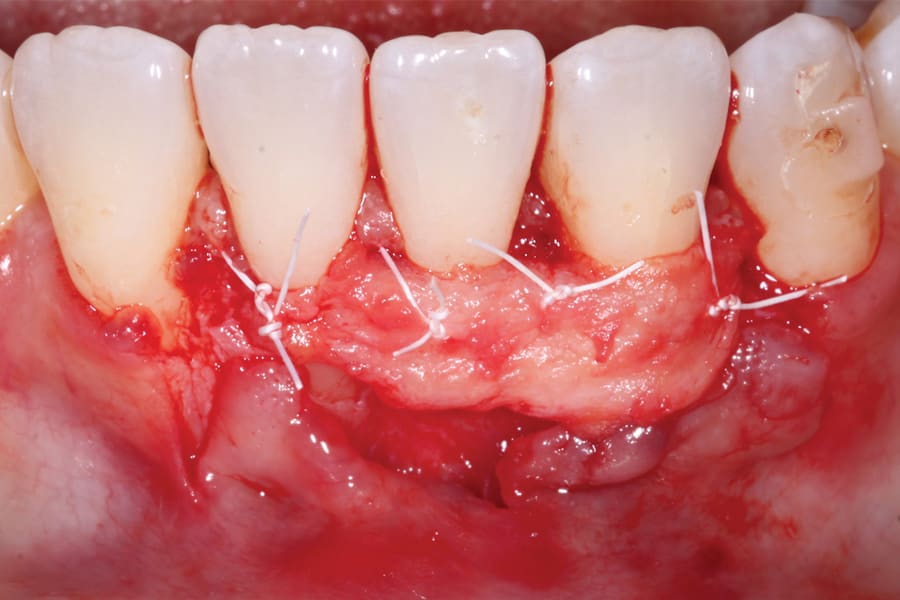

Although spontaneous improvement of the investing tissues is often observed through orthodontic correction (Figure 7 and Figure 13),5 additional corrective action is frequently indicated afterwards, particularly when cosmetics are to be considered. A recession defect case is depicted in Figure 17 through Figure 26 in which corrective action was necessary and accomplished through aligner therapy followed by connective tissue grafting.6 It should be noted that although this corrective scheme may successfully achieve an acceptable cosmetic and functional result, it is not likely a regenerative outcome in the sense that a previously dehisced root surface typically will not attain ligamentous insertion into freshly laid cementum. A long junctional epithelium or connective tissue attachment at best is the more likely outcome. Consequently, a preventive approach initially would be more desirable.